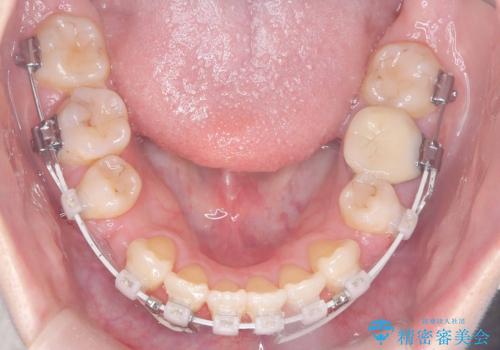

- 「歯のデコボコ、八重歯、口ボコが気になる」を主訴に来院された患者様です。

上下左右4番(4本)の歯を抜歯しワイヤー矯正で治療を行いました。

計4本の抜歯を行い、歯のデコボコと口元がすっきりし、大変ご満足していただけました。